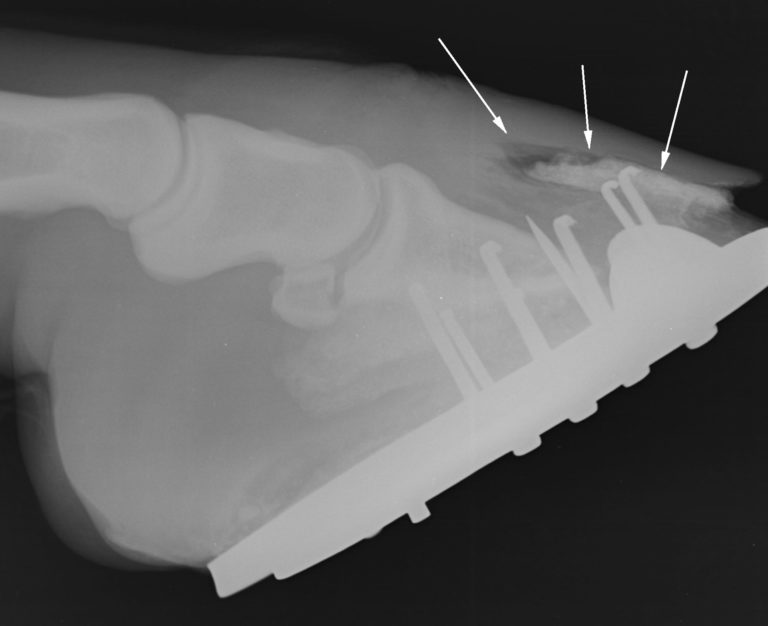

Severe hoof infection penetrated by the white line, infection by anaerobic bacteria (bacteria that can live without oxygen) and fungi that are resistant to local antibiotics and antifungals.

The treatment of this pathology involves eliminating all the affected tissue and invaded by fungi and bacteria, to expose them to the action of a caustic that they completely eliminate.